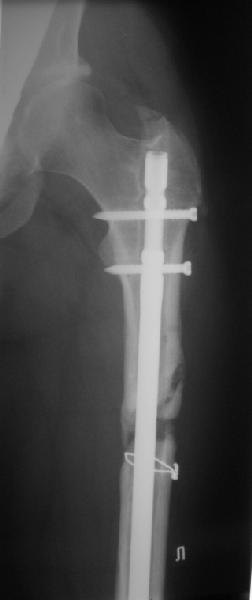

Пациент попал под наше наблюдение через 3 недели после первого остеосинтеза (фото 1). Учитывая, нестабильность остеосинтеза, выстоящий стержень закрыто перештифтовали (фото 2), через 3 месяца динамизация. К 5 месяцам имели укорочение 2 см, при том, что динамический винт стал статическим. От дальнейшей динамизации отказались, учитывая наличие контакта между фрагментами и возможность прогрессирования укорочения. К 1,5 года сращение не достигнуто (фото 3). Удалили гвоздь, выполнили дистракционный остеосинтез с целью стимуляции остеогенеза и компенсации укорочения (фото 4), потом закрыто перештифтовали после рассверливания (фото 5). На сегодняшний день, через 4 месяца после последней операции (фото 6) признаков регенерата нет, длина восстановлена, ходит без дополнительной опоры.